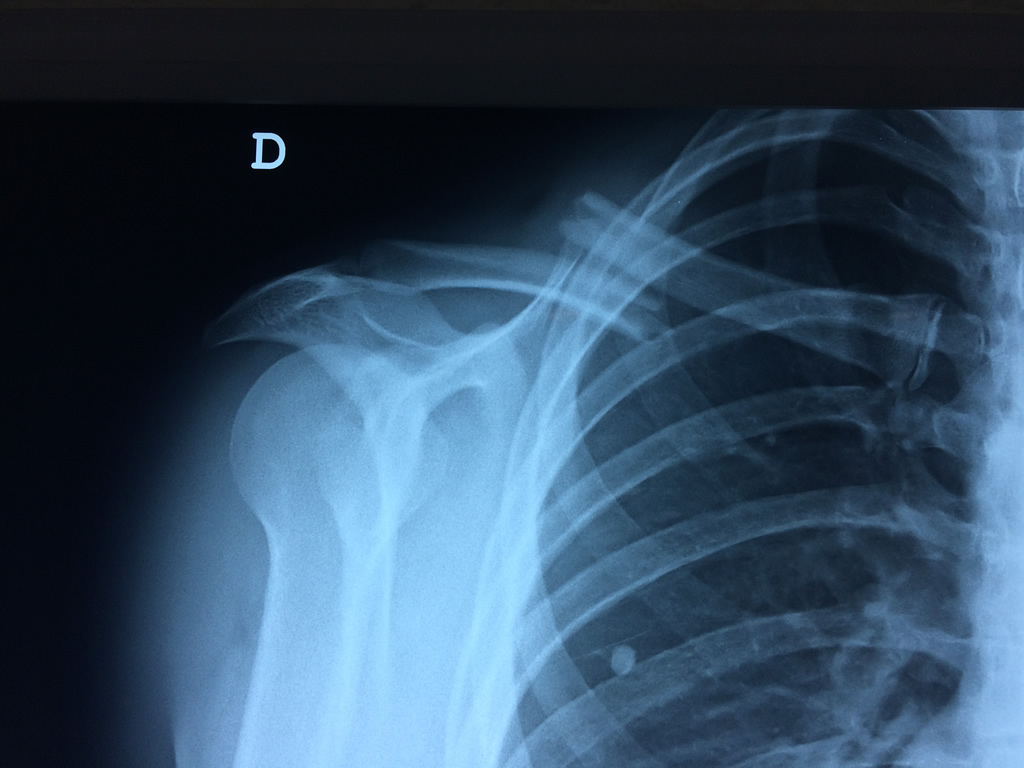

La clavícula es un hueso largo, con forma de "S" itálica, situado en la parte anterosuperior del tórax. Junto con la escápula forman la cintura escapular. Se puede palpar por toda su longitud y se extiende del esternón al acromion de la escápula, siguiendo una dirección oblicua lateral y posterior.

Se considera el único medio de unión entre el miembro superior y el tórax. A pesar de su aspecto, similar al de un hueso largo, posee una estructura semejante a la de un hueso plano, ya que carece de epífisis y de diáfisis, lo que la harían entrar dentro de la clasificación de hueso largo. Carece de un canal medular propiamente dicho.